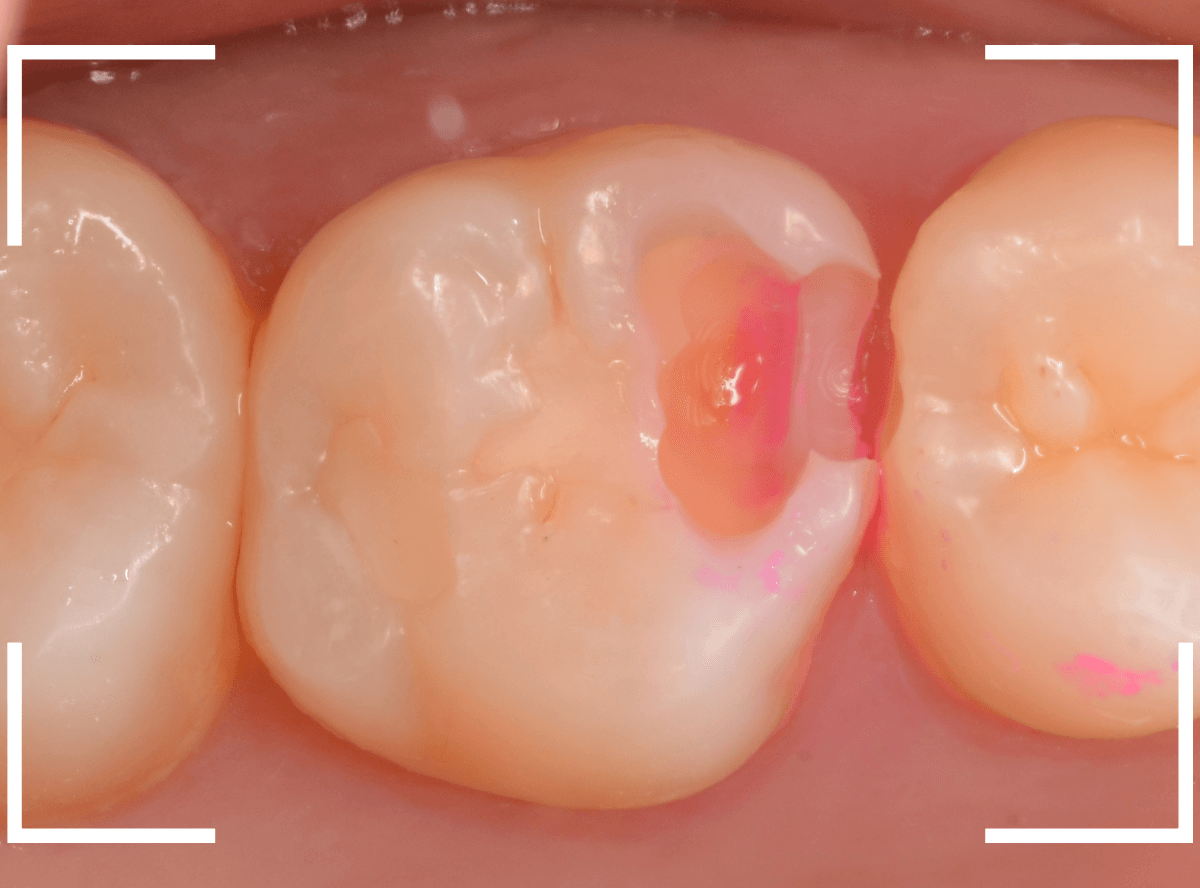

手前の歯まで虫歯を除去した時点で、う蝕検知液で確認します。

赤く染色されている部分が虫歯です。

思ったよりも深めの虫歯ですね。